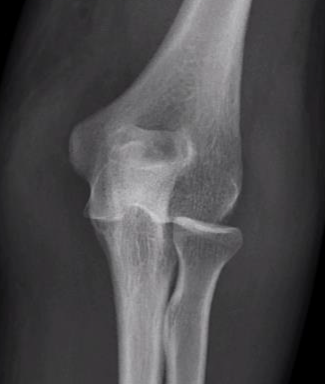

Simple elbow dislocation

Second most common dislocation after shoulder

Most common 10 - 19 year age group

FOOSH

Posterior / posterolateral Complete Simple - no fractures

Final position of ulna relative to humerus Subluxed / perched 10% Complex - fractures